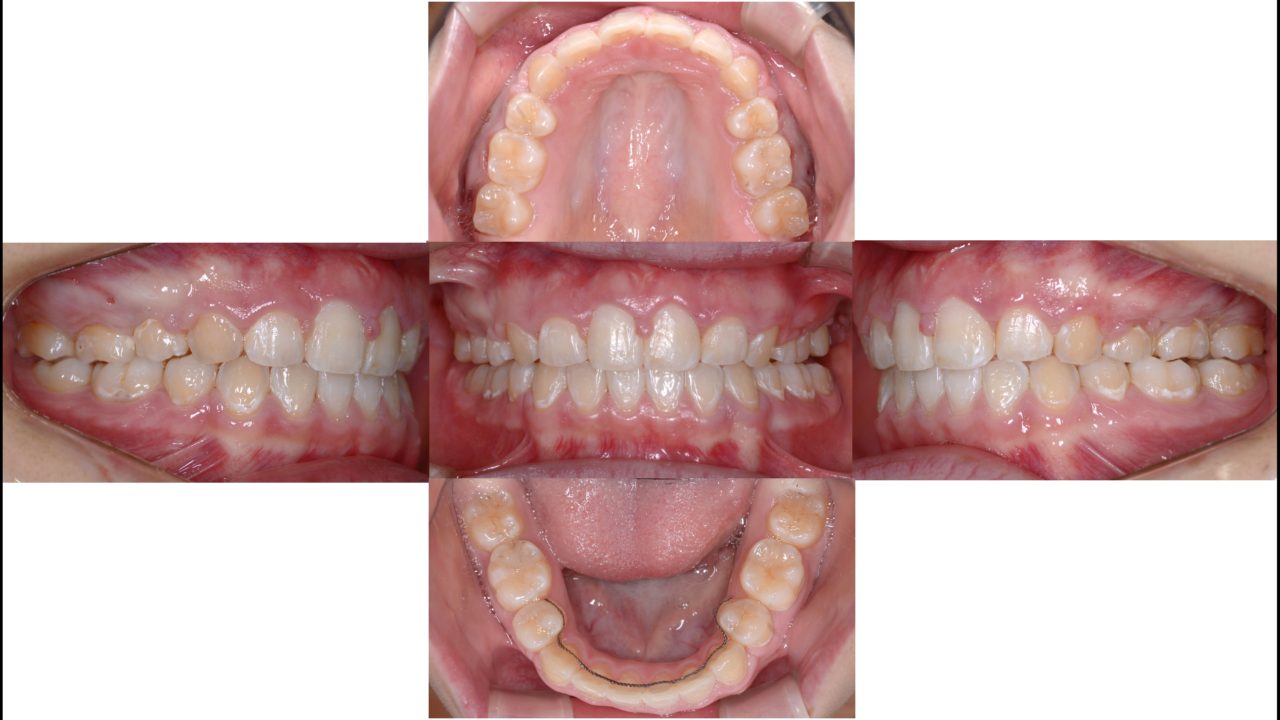

After

矯正終了 2020.7.2

| 備考 | 小学生のときに他院で第1期矯正をされていました。歯の凸凹は治り歯列はきれいになりましたが、全体的に前に出た仕上がりに不満を持っていました。成長の予測が難しい第1期矯正において、起こりうることです。口元をきれいに引っ込めるために抜歯を伴う矯正治療をすることになりました。第1小臼歯を4本抜歯し、矯正用インプラントにてできるだけ前歯を後方に移動しました。口元が引っ込み、とてもきれいになりました。矯正治療のやり直しはできればしたくないし、さらに結果が求められるので大変ですが、良い結果が出てよかったです。 |